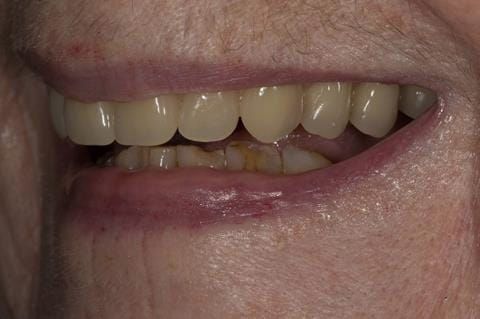

Following consultation and second discussion appointment the patient chose to have option 2 namely, a window denture - maxillary cobalt chromium based partial denture. The clinical situation and treatment process is shown in detail below with photographs. The patient was successfully rehabilitated with this and her quality of life considerably improved. The clinical work was provided by Finlay and the technical work by Rowan.